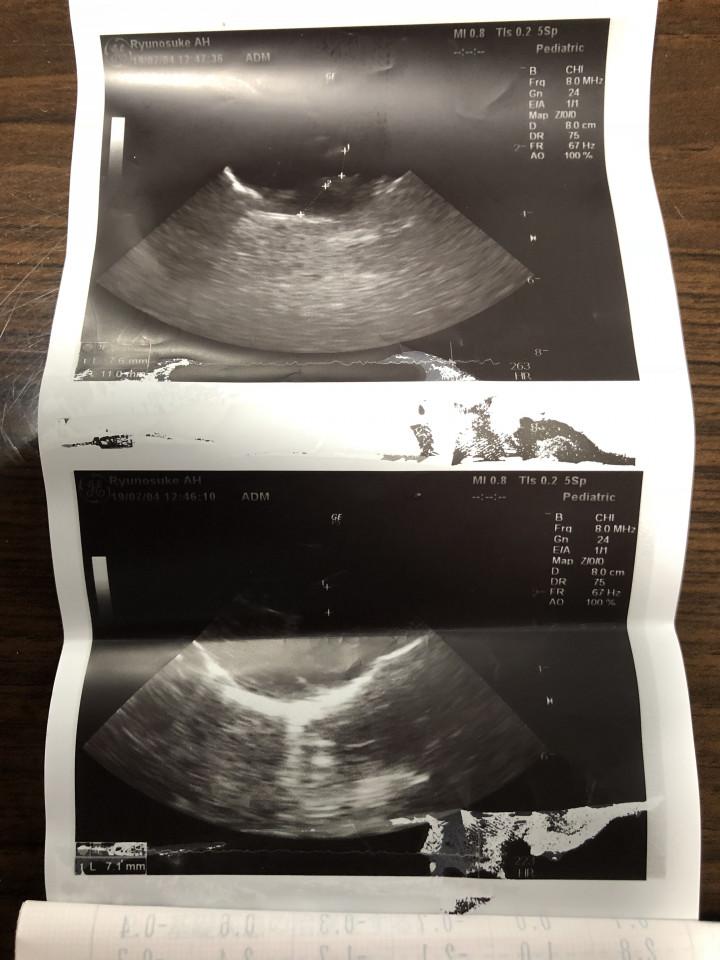

先生がエコーで見たけど

特に心配いらないみたい。

「落ち着いて聞いてくださいね。

本来、咳が出る原因を調べるために

レントゲンを取りました。

レントゲンでは肺に異常は

なかったんですよ。

ただ……

この子の心臓なんですが……

大きすぎなんです。

普通の子の2倍はあるでしょうか……

萎んだレモン位が

通常の心臓の大きさです。

かなり大きいですよね……」

※赤いのが通常の大きさらしい。

ぷりんのは明らかに大きい!

心電図取りました。

不整脈は出ていません。

心筋の厚さも基準値内でした。

コレも確認してください。特に

今のところ問題はないようです。